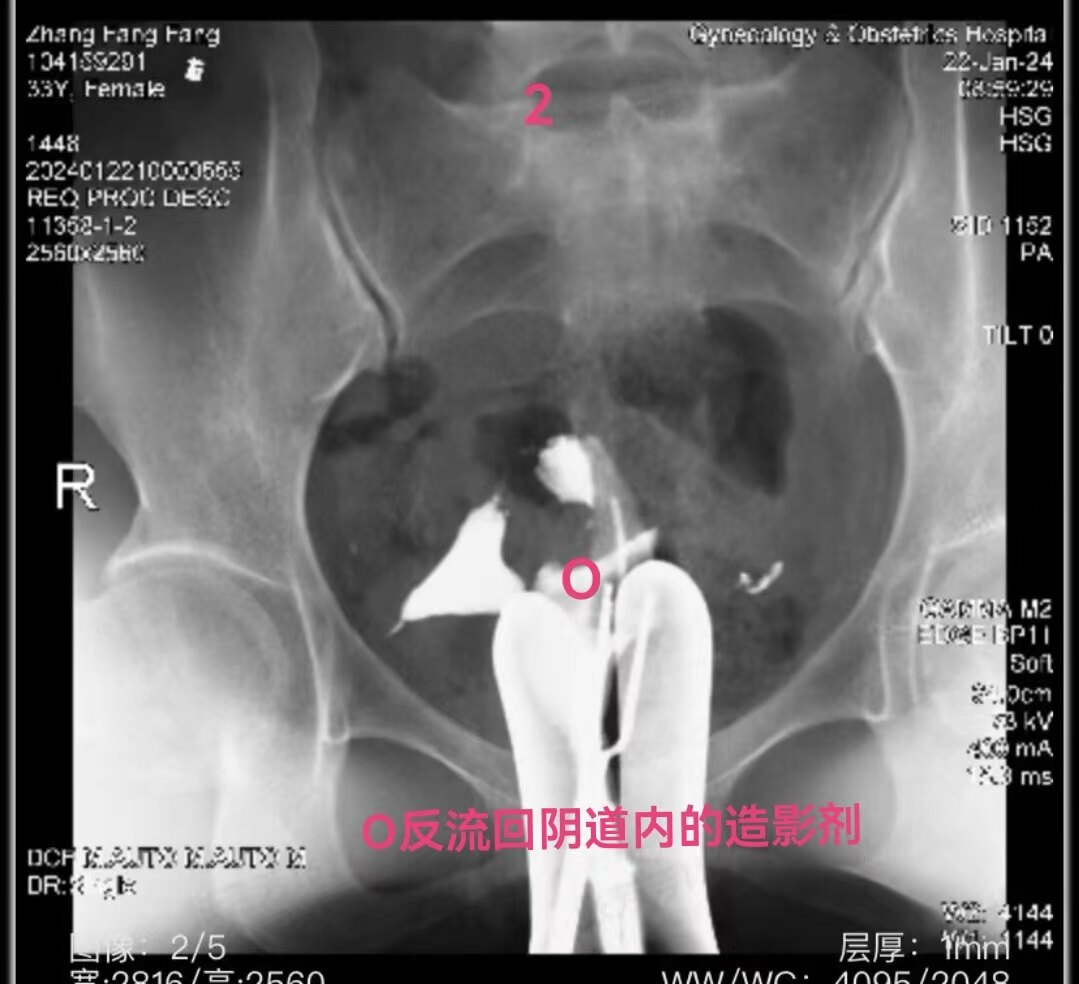

22.jpg

左侧输卵管显影至壶腹部,右侧输卵管显影至峡部。造影剂返回到阴道

2.jpg